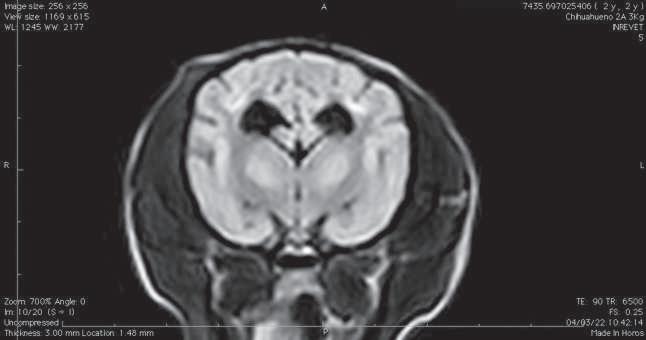

Figura 1. (A y C) Imágenes ponderadas en T2W. (B y D) FLAIR con lesiones hiperintensas en múltiples regiones encefálicas asociados a focos de edema con mayor evidencia en núcleos basales y tálamo (A, B) y lóbulos parietales y temporales (C y D).

Figura 2. Imágenes ponderadas en T2W (A, C) y FLAIR (B, D) en las cuales se aprecia una disminución en las lesiones hiperintensas descritas en la figura 1.

Conbasealosresultadosderesonancia magnética (Figura 1), raza y hallazgos neurológicos los pacientes fueron diagnosticados con enfermedad inflamatoria cerebral (Meningoencefalitis de origen desconocido) e iniciaron con una terapia basadaenStee2020,10 conlacombinación decitarabina(Cytosar-U®Pfizer500mg) a dosis de 100/m2 y prednisona a dosis de 1 mg/kg iniciales por 4 semanas (dosis reducción a 36 semanas), para posteriormente evaluar la evolución clínica del paciente y por imagen con las mismas indicaciones de resonancia previamente descritas.

En el presente estudio 5 de 6 pacientes mostraronunamejoracínicasignificativa, enunpaciente(Shih-tzu)elcualingresóen estatus epiléptico no presentó más crisis convulsivas ni se han reportado hasta el momento, el estado mental de los 6 pacientes mejoró de forma significativa, sólounpaciente(Yorkshire)conimágenes por resonancia magnética con herniación subfalcina continuó con giros, los déficits propioceptivos continuaron en 2 de 6 pacientes (Cuadro 3). En las imágenes por resonancia magnética posterior a las 4 semanas iniciado el tratamiento se vio unadisminucióndeledemareportadoque va desde el 85% hasta 50% (Figura 2).

El propósito del presente estudio fue determinar la relación entre la respuesta clínica y la evaluación de las imágenes por resonancia magnética en estudios seriados usando un protocolo de tratamiento basado zen las regiones con hiperintensidad enT2Wfue notoria en la mayoríadeloscasosdescritos.Sepresentó una predilección en hembras (4 de 6) como varios estudios han reportado.1,7,11 Dos casos se presentaron con convulsiones agudas sintomáticas, uno de ellos en estatus epiléptico, Kaczmarska, et al., reportaron una prevalencia del 50% de convulsiones,5 en algunos otros reportes varía del 23% al 37.5%.12,13 Se ha informado que la RM tiene una sensibilidad

del 94.4% y una especificidad del 95.5% para detectar una anomalía cerebral, con un rendimiento similarmente alto para clasificar enfermedades neoplásicas e inflamatorias,14 aunque actualmente no hay información disponible sobre el uso deresonanciamagnéticaparadiferenciar entrecasosconfirmadoshistopatológicamente de MEG, MEN, LEN.